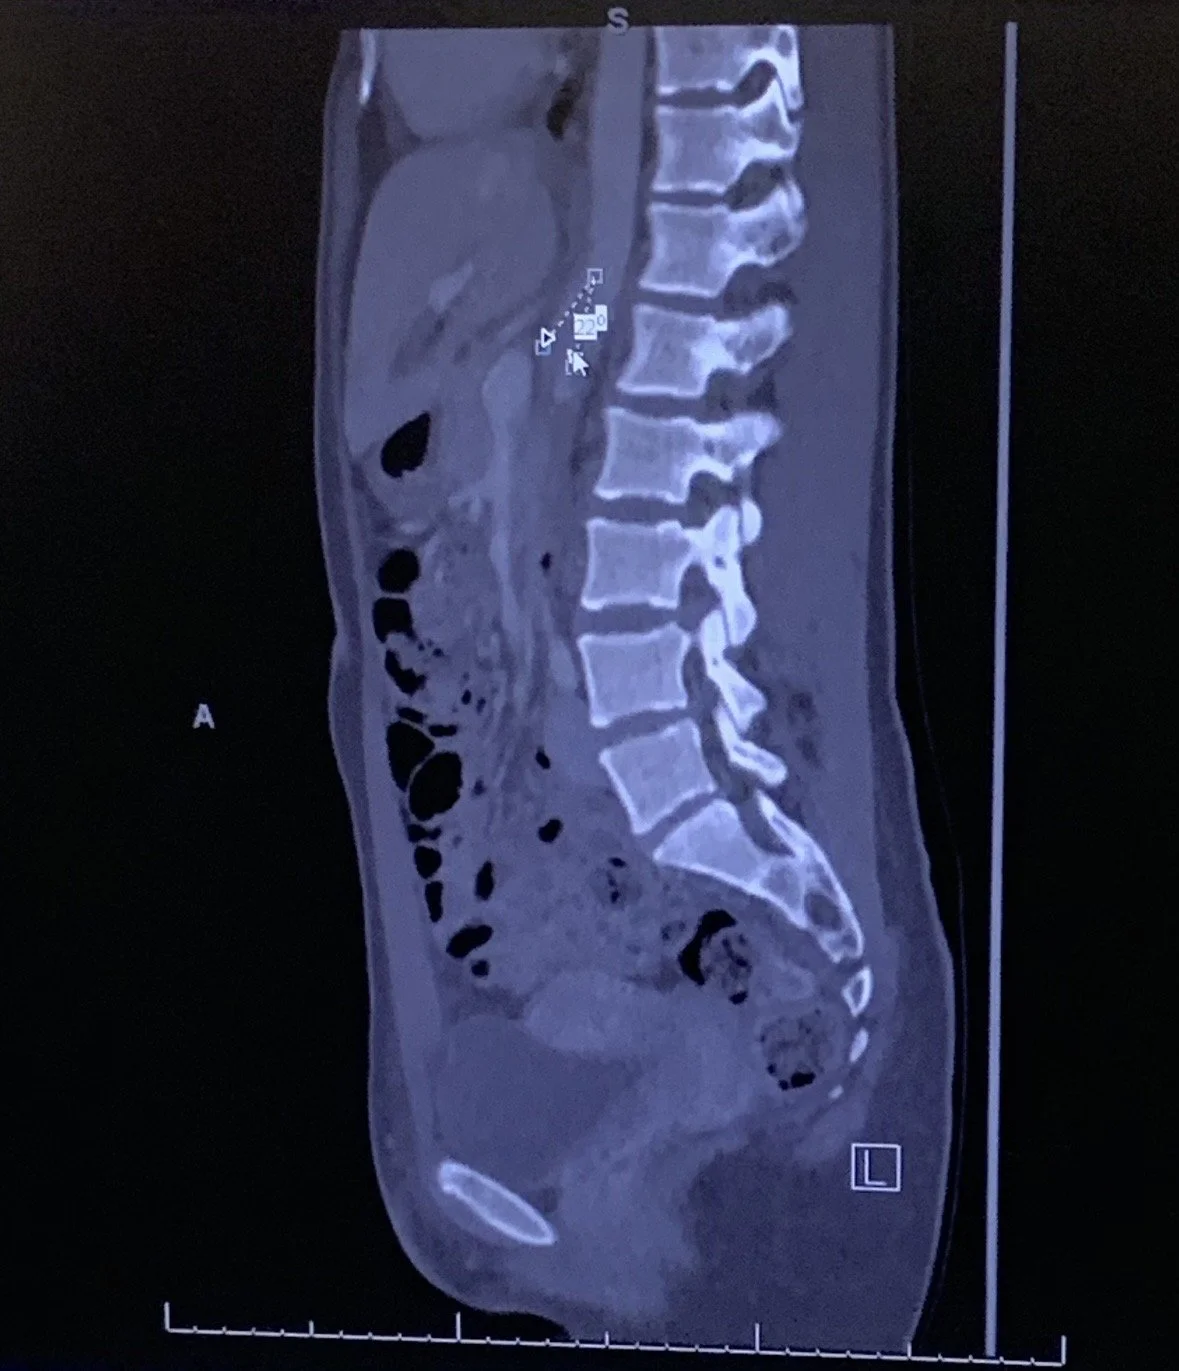

Before I dive into what the imaging in London revealed, I’ll explain what my hospital CT scan did catch – even though it was overlooked at the time.

The radiologist noted that I have a lack of mesenteric fat. For most people, this is an incidental finding, insignificant. For me, it explained why I crashed after eating wagyu in Bali.

Years earlier, a specialist realized I have all of the symptoms of Superior Mesenteric Artery (SMA) Syndrome and Nutcracker Syndrome – rare anatomical variants where the angle between the aorta and superior mesenteric artery is too narrow.

This causes compression of the small intestine and left kidney vein as they pass through that space. The lack of mesenteric fat means there's no cushion protecting them.

My symptoms dated back to age 8 (abnormal urine at my first checkup), but it took until I was nearly 30 to get the anatomical confirmation. The photo below is a photo I took where my hepatobiliary and pancreatic specialist was showing me my narrow angle.